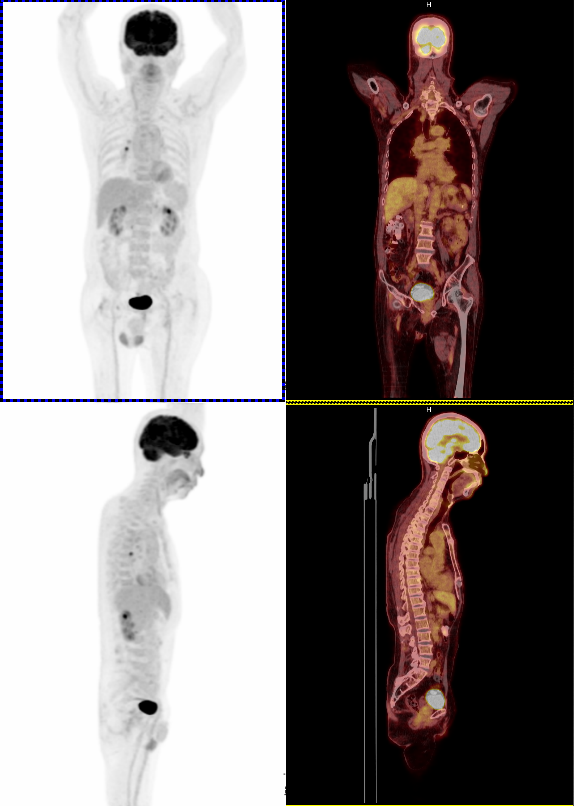

正子電腦斷層掃描儀

早期診斷癌症的非侵襲性全身健檢利器

「正子造影」的全名是「正電子放射斷層攝影( Positron Emission Tomography )」,簡稱PET,是現今最先進的醫療診斷技術之一,林新醫院引進德國SIEMENS公司的Biograph Horizon 正子電腦斷層掃描儀,使用獨特的LSO晶體有更高的光輸出,搭配Time-of-Flight 及HD PET技術影像清晰度並縮短檢查時間。syngo.via自動化進行項處理,為您獲取更多精確腫瘤吸收變化資訊。